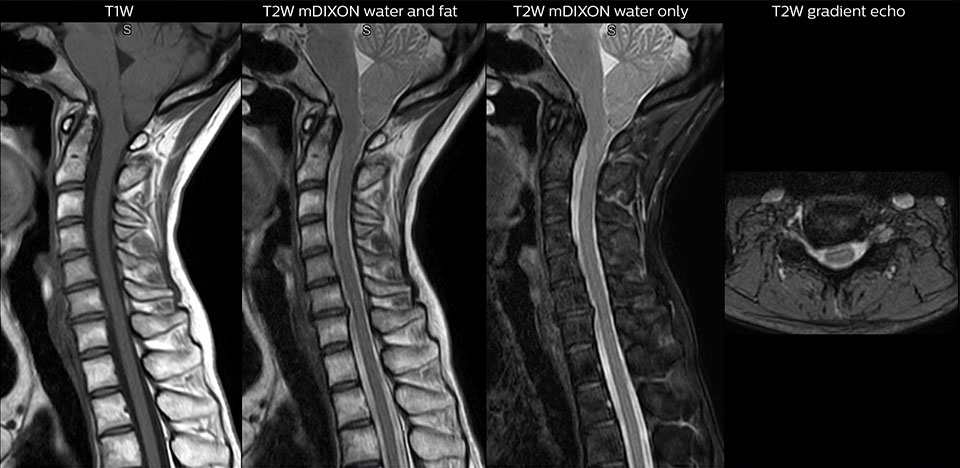

„mDIXON TSE wird in unserer Notaufnahme ausgiebig für die Wirbelsäulenbildgebung eingesetzt“, führt Dr. Karis aus. „Besonders vorteilhaft ist, dass dieses Verfahren im Hinblick auf suszeptibilitätsbezogene Probleme sehr stabil ist, die häufig bei klassischen spektralen, fettgesättigten Bildern auftreten. Im Wesentlichen treten derartige Probleme beim mDIXON-Verfahren überhaupt nicht auf. Wir sind wirklich froh, in unserer Notaufnahme über die fettfreie Bildgebung des mDIXON-Verfahrens zu verfügen.“

„Für die routinemäßige, kontrastmittelfreie Untersuchung der Brust- und Halswirbelsäule führen wir zum Beispiel eine mDIXON T2-TSE-Sequenz durch, die uns zwei Ergebnisse liefert: die T2-gewichteten Bilder auf Fett- und Wasserbasis sowie die sagittalen T2-gewichteten Bilder auf reiner Wasserbasis. Anschließend erfolgt noch eine axiale Gradientenecho-Untersuchung.“

Routineuntersuchung der Halswirbelsäule

Dieser Patient wurde mit Kopfschmerzen vorstellig, die sich bei einer Flexion des Nackens verschlimmerten, und wir sehen hier eine Chiari-Malformation vom Typ I mit niedrig liegenden Kleinhirntonsillen sowie degenerativen zervikalen, thrombolytischen Veränderungen.